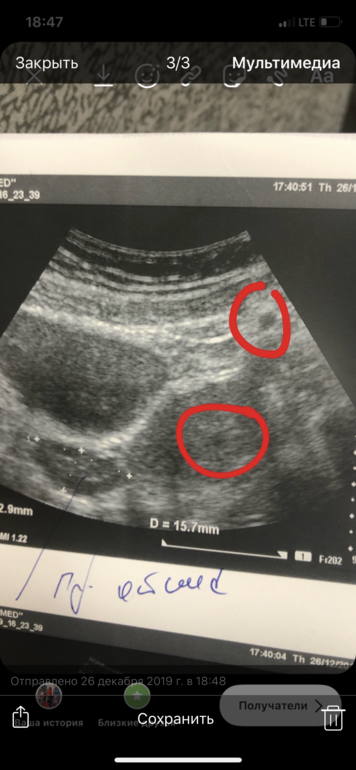

Сверху красный обведено это жт ?? Или что это . 2 пятна . Одно сверху возле левого яичника . Второе в матке . Узист не объяснила что это ((((